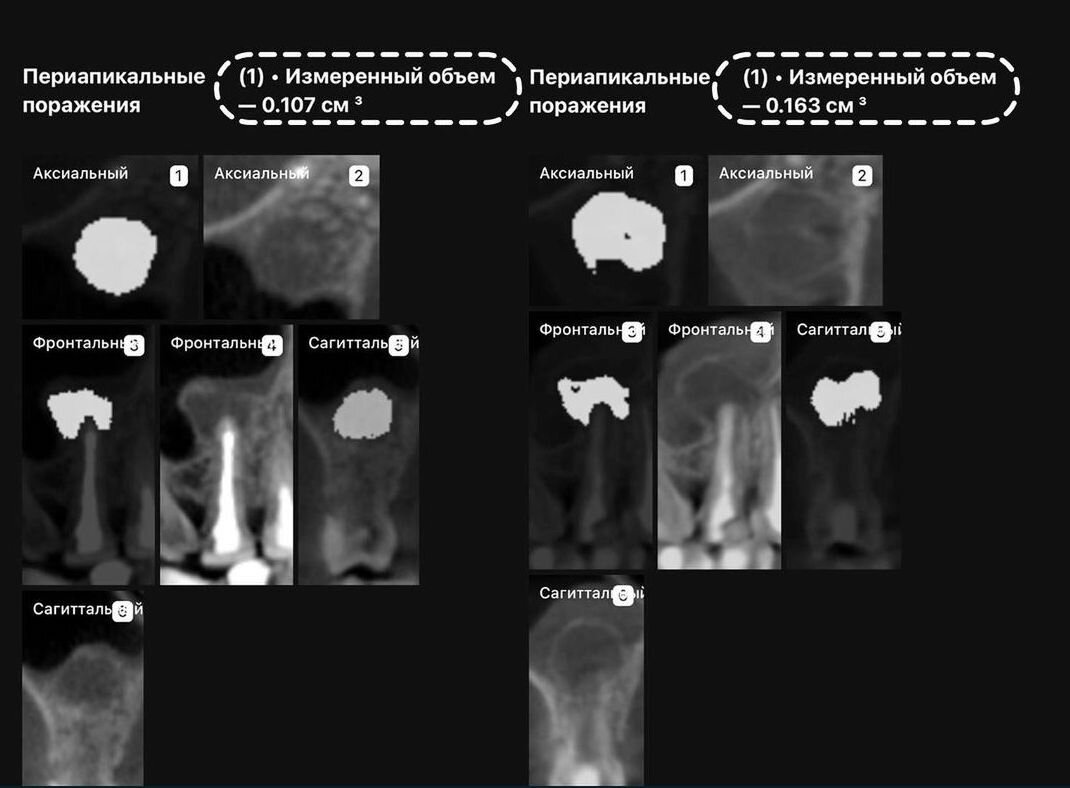

Рис. 6.1. Хронический апикальный периодонтит зуба 44